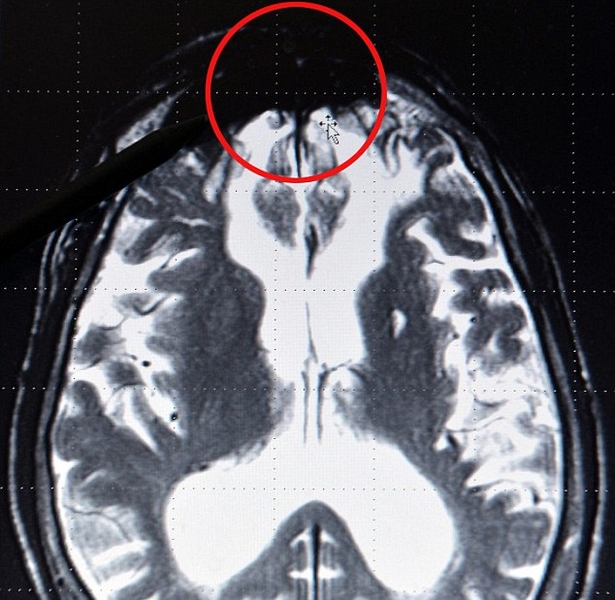

Причина оказалась темной. И речь в данном случае идет не столько о темной биографии, сколько о темном пятне в мозгу маньяков. Такую область обнаружил немецкий ученый, изучая рентгеновские снимки различных областей головного мозга. Подозрительный участок находится в центральной доле мозга преступников.

Открытие дело Герхарду Роту повод предположить, что именно в этой затемненном сегменте и кроется разгадка человеконенавистничества убийц, а склонность к убийству имеет генетическую природу.